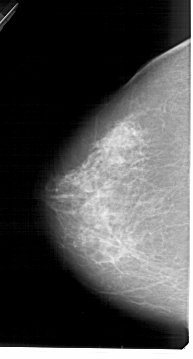

A_1458_1.LEFT_MLO

LEFT_MLO LINES 5491 PIXELS_PER_LINE 3106 BITS_PER_PIXEL 12 RESOLUTION 43.5 NON_OVERLAY